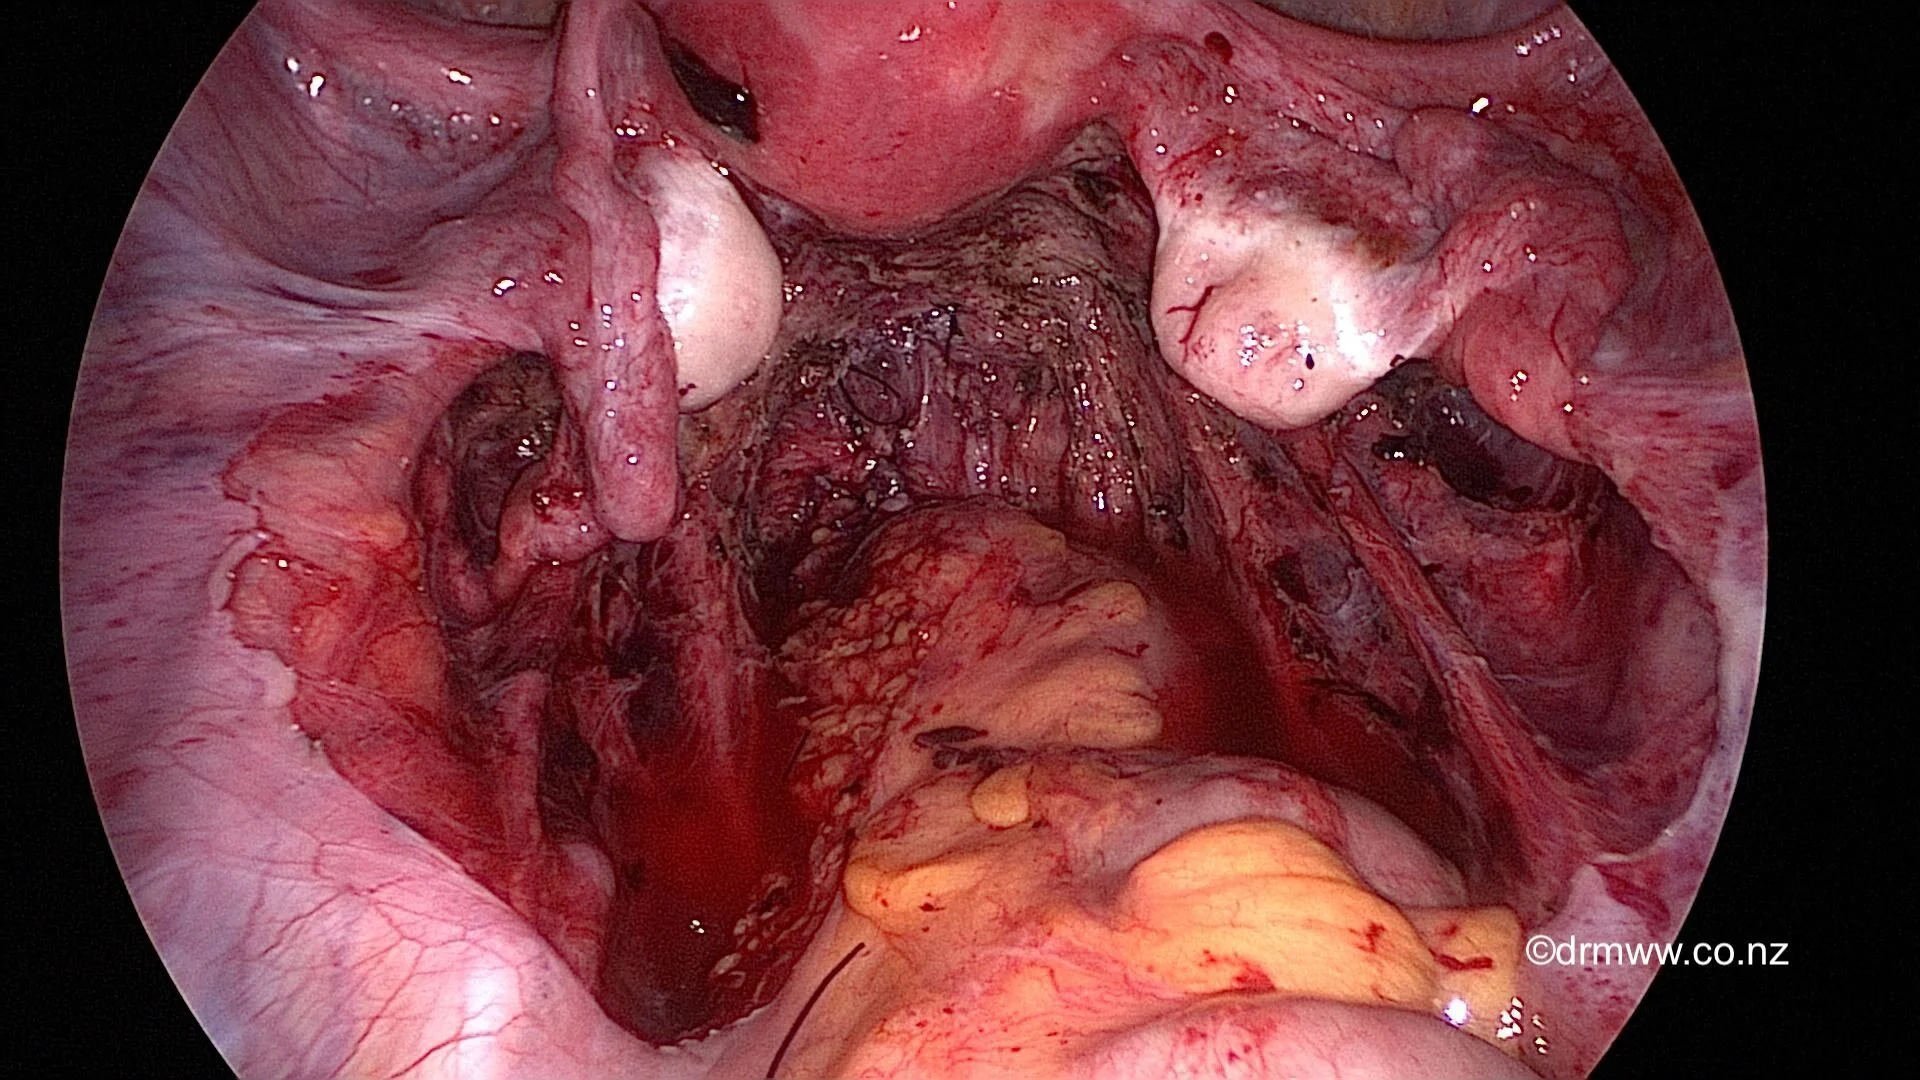

A pelvis after complete excision of endometriosis, including shaving of the above rectal muscularis nodule.